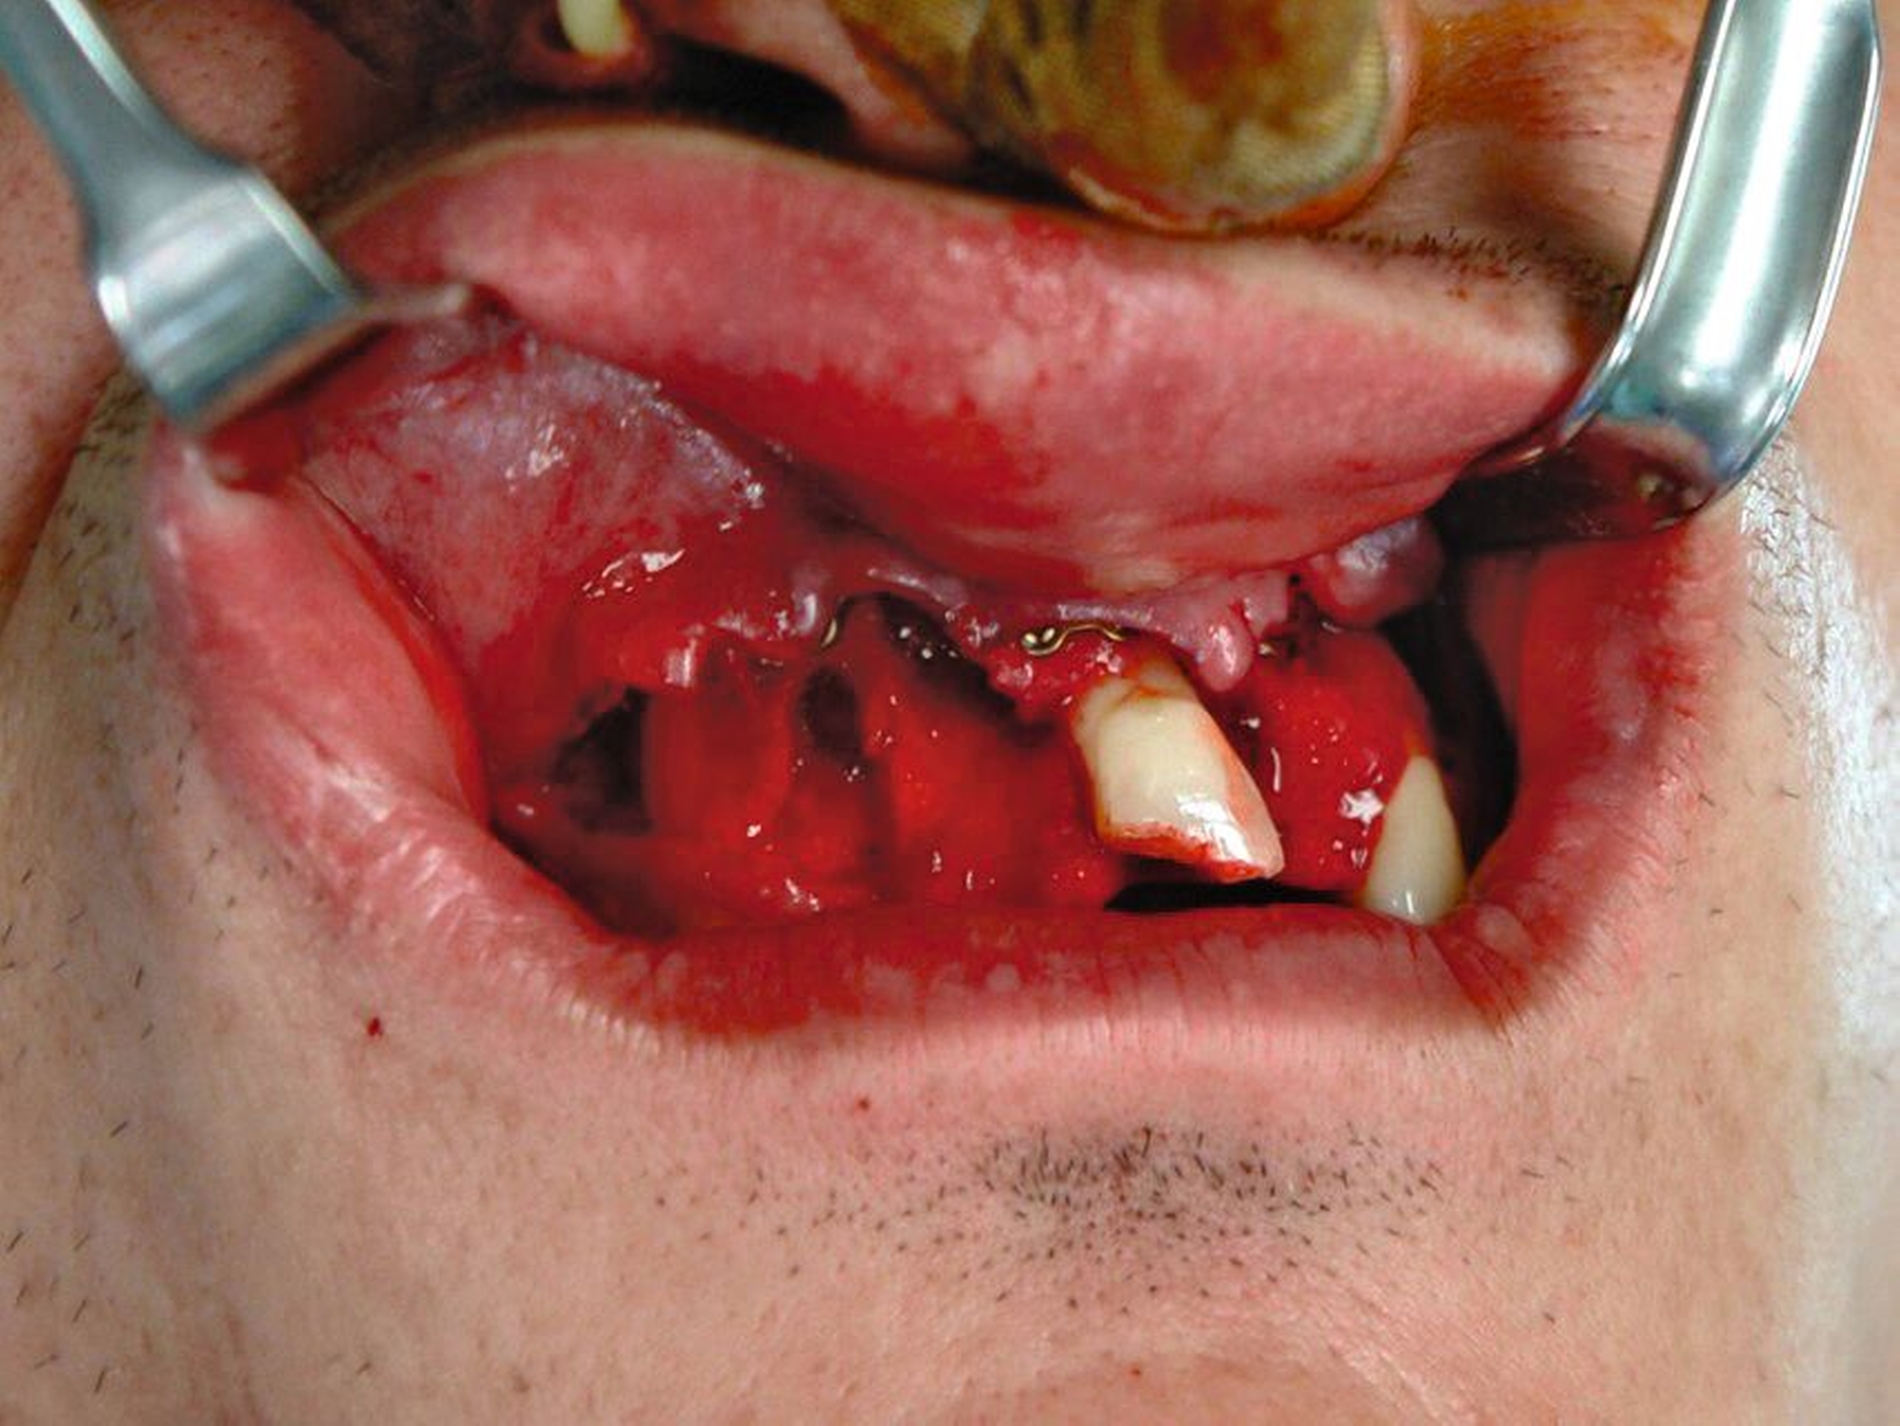

Nach der Einschätzung der Zellvitalität auf der oben genannten Basis folgt die therapeutische Intervention im Sinne der Replantation des betroffenen Zahnes in die gespülte Alveole (vorsichtige Entfernung des Blutkoagulums) mit steriler physiologischer Natriumchloridlösung. Schließlich muss die Replantation schonend erfolgen, da immer mit daran gedacht werden muss, dass es im Rahmen des Traumas zusätzlich zu einer Schädigung des Alveolarknochens gekommen sein kann (Abbildung 1). Diese Schädigung kann eine vollständige oder teilweise Alveolarfortsatzfraktur sein, die entsprechende Beachtung finden sollte. Im Anschluss erfolgt die Schienung des betroffenen Zahnes an den Nachbarzähnen. Dabei sollte ein Zeitraum von ein bis drei Wochen eingeplant werden (Tabelle 1).

Die Replantation sollte langsam und mit wenig Druck erfolgen, um eine zusätzliche Schädigung des Wurzelzements zu vermeiden. Anschließend sollte eine flexible Schienung des Zahnes erfolgen (Empfehlung 50) [Kahler et al., 2016].